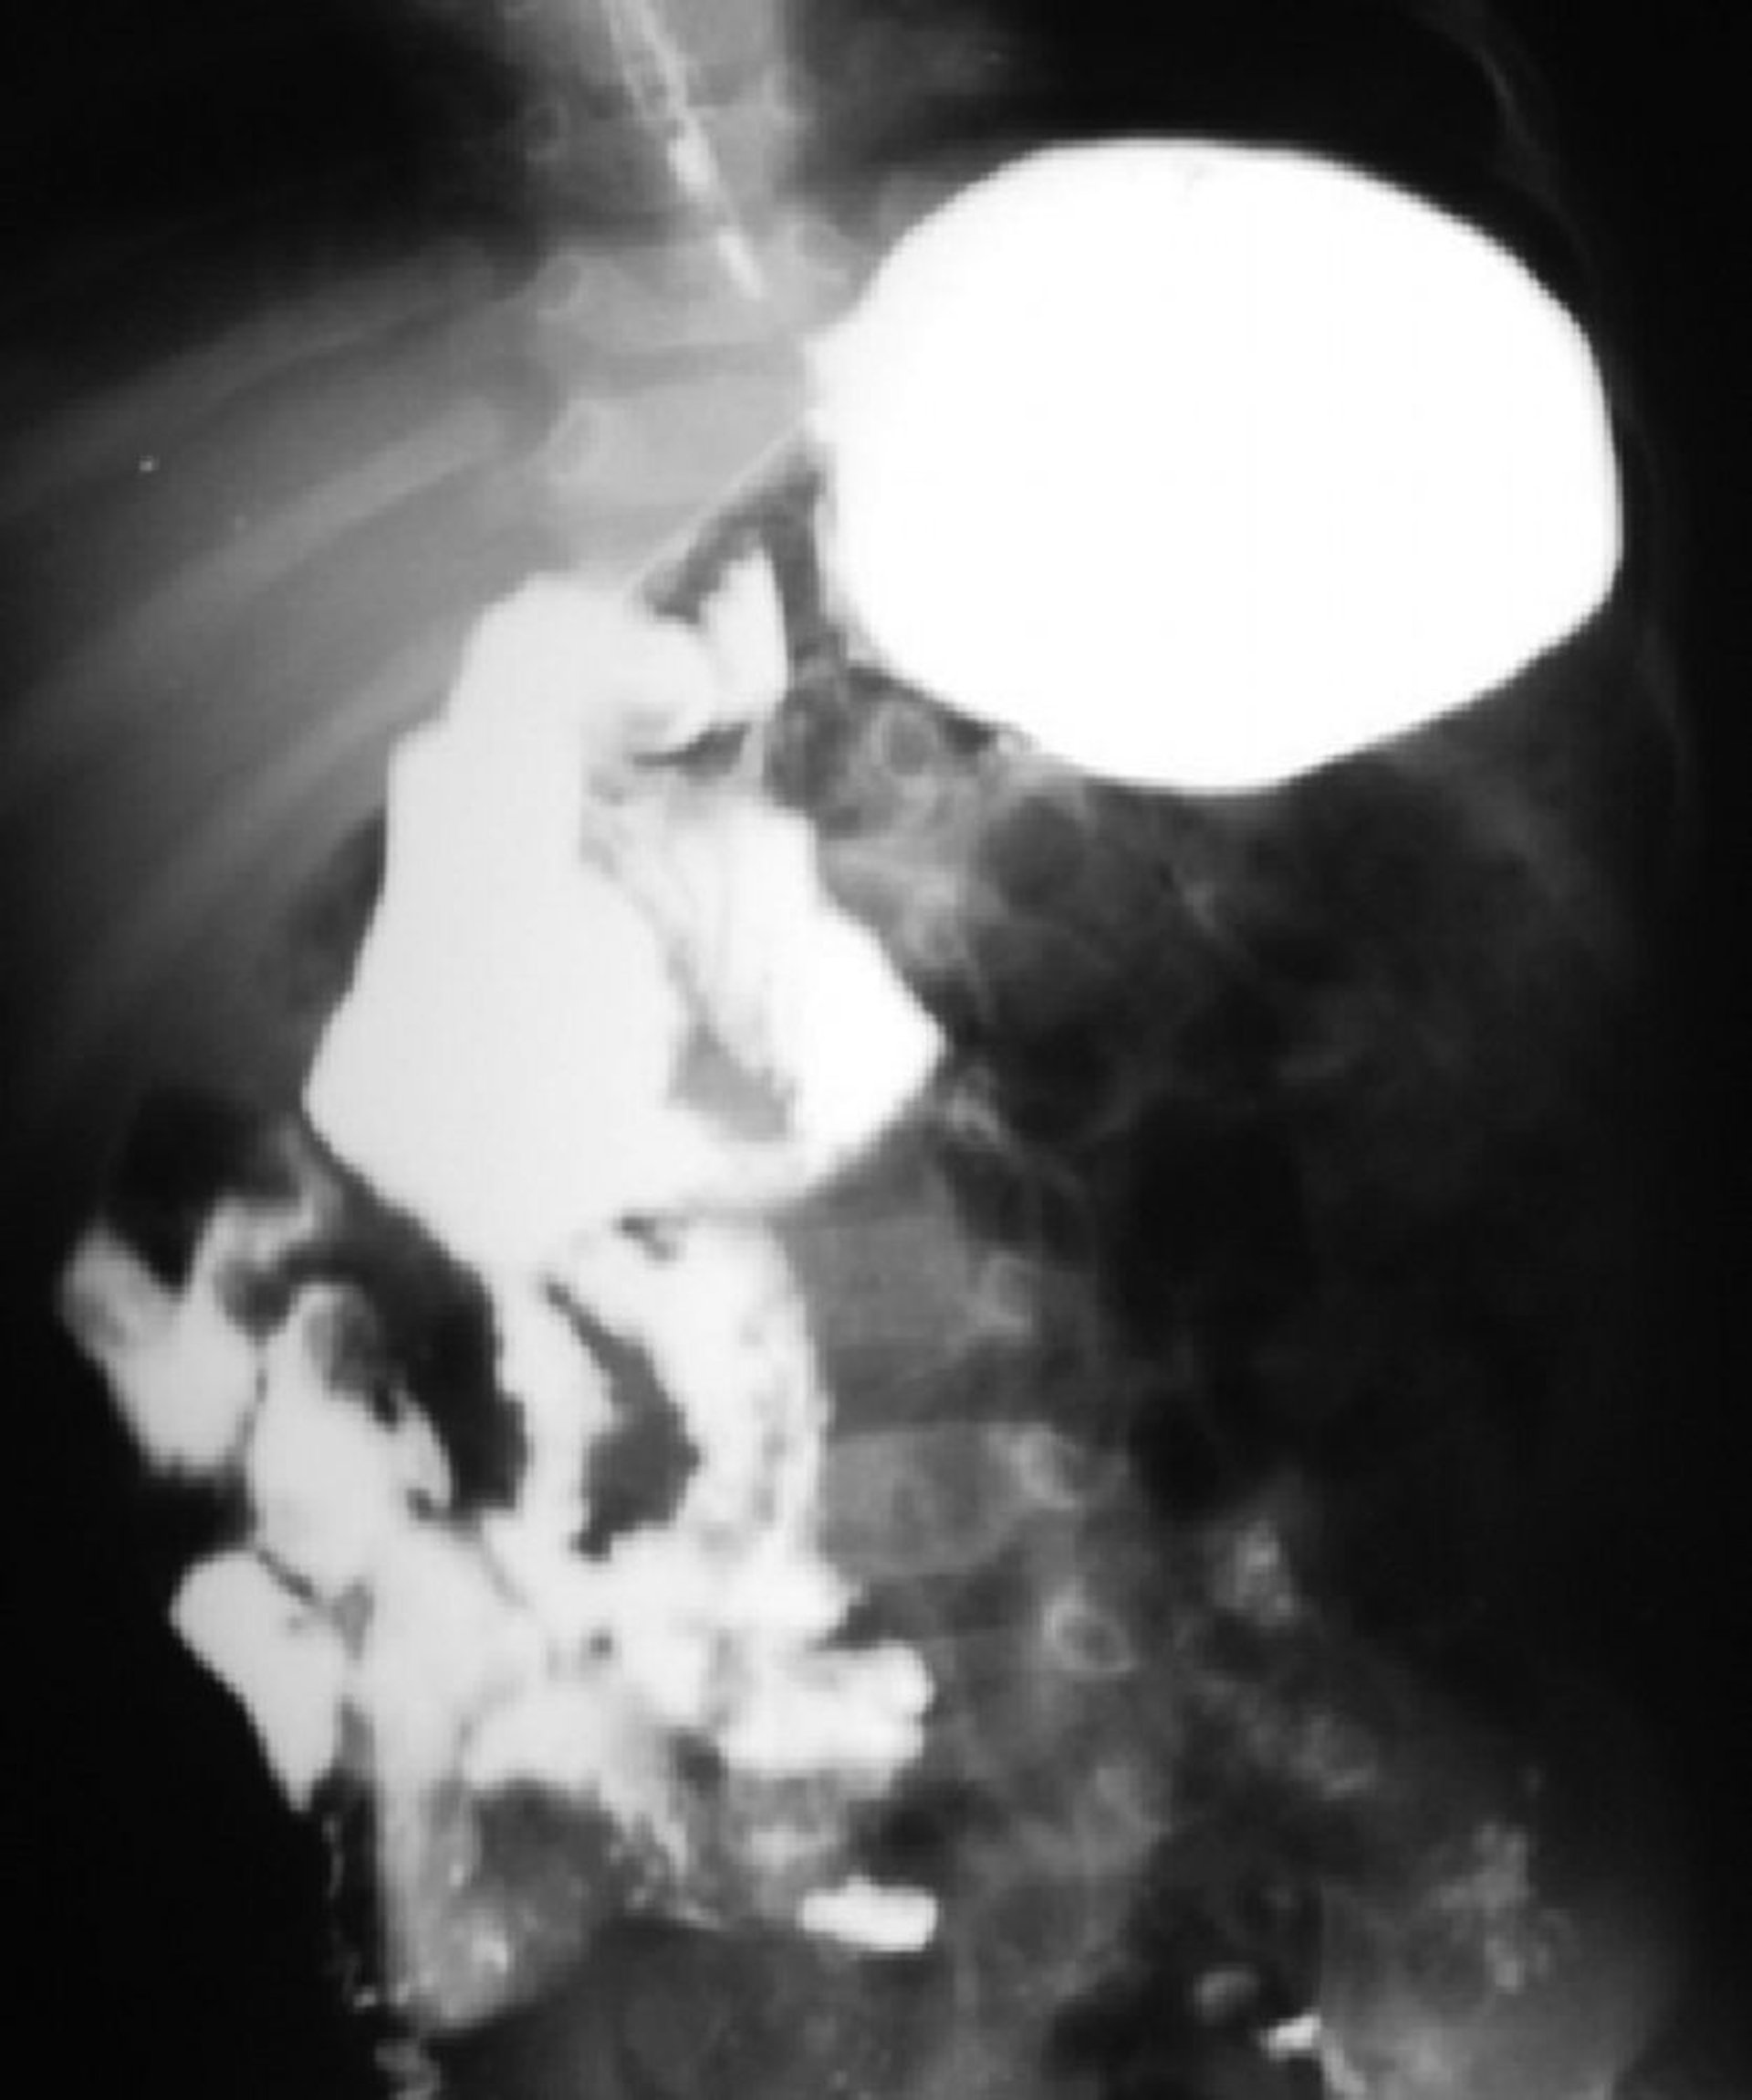

Má rotação do intestino

Esse exame com bário mostra má rotação do intestino. A junção duodenojejunal está à direita da coluna, e a maior parte do intestino delgado está à direita.